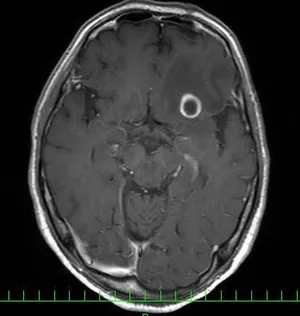

頭部造影MRI検査画像 頭部造影MRI検査画像 頭部造影MRI検査画像

頭部造影MRI検査画像(肺がん脳転移)